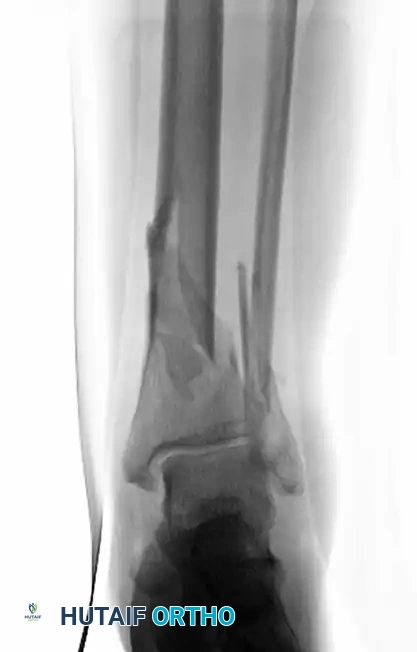

MINIMALLY INVASIVE PLATING OF TIBIAL PILON FRACTURE Surgical Diagram

Figure 54-17 A: Initial presentation of a closed, highly comminuted fracture involving the tibial pilon and fibula.